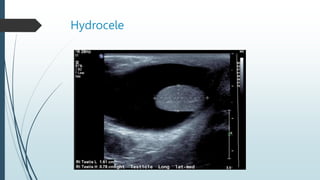

Hydeocele

A hydrocele is the formation of fluid between

the two layers of tunica vaginalis.

Ultrasonographically it is seen as echo-free

area partly surrounding the testicle.

It may develop from

,trauma,infection,malignancy,infarction,etc.

Hydrocele